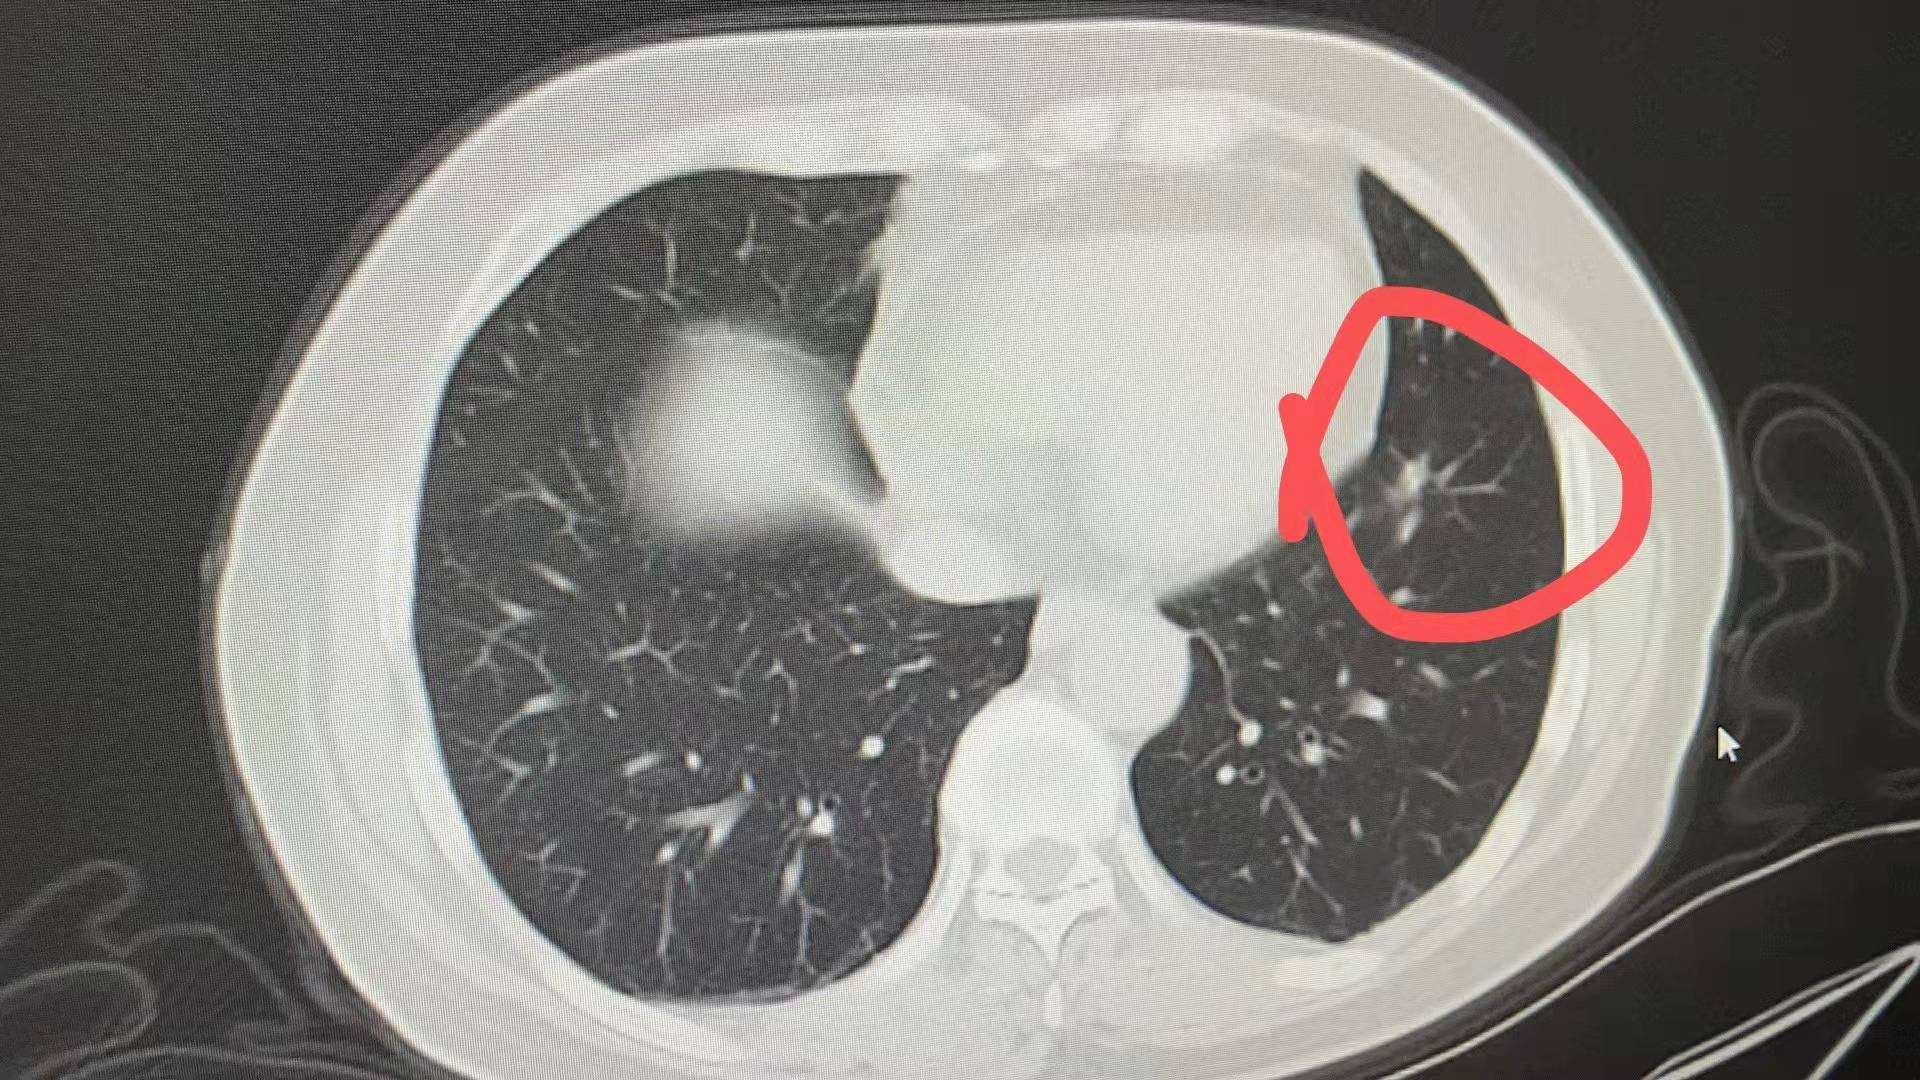

增强CT:肺窗截面8.7mm*5.2mm,多发磨玻璃结节4mm。初诊增强CT:肺窗截面18mm*13mm,多发磨玻璃结节4mm,左肺门淋巴转移23*16mm,纵膈淋巴结转移短径12mm,骨骼转移需观察,明显好转有效治疗[胜利]